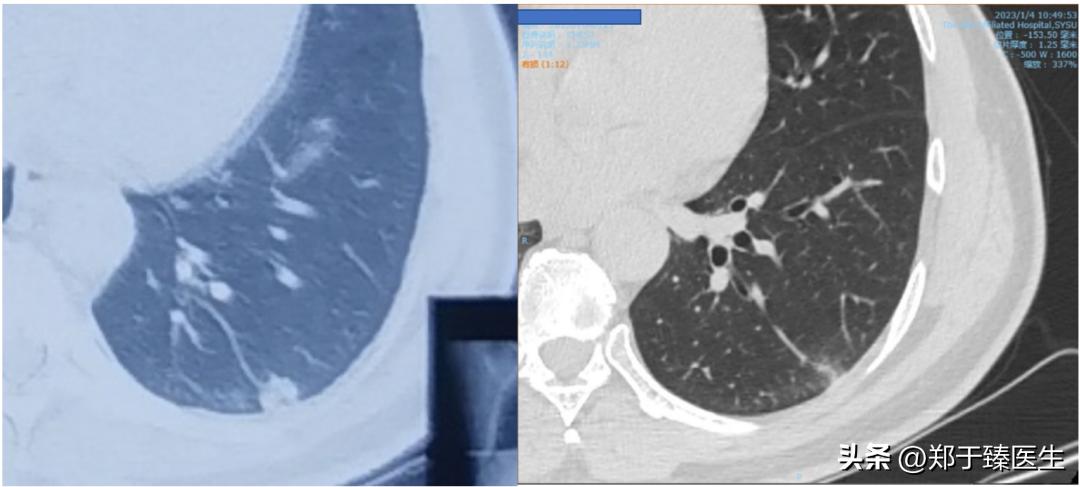

12月下旬,患者联系我,说自觉胸闷不适,我担心体内遗留肺炎情况,因此建议他复查了个CT(2022.12.25),结果一看,果然出现肺炎了。

于是,我尽快给他安排住到我们医院,在和主管医生沟通后,查了核酸阴性,于是就上了小剂量激素配合抗生素进行处理(2022.12.26开始)。

一周后,复查CT,炎症消退,患者症状明显好转,办理出院(2023.1.4)。

前后治疗周期10天。

从CT的片子来看,炎症几乎全部吸收,甚至连胸膜下线都没有看到,这说明实变区域吸收非常彻底,没有遗留任何纤维结缔组织,也就是没有任何后遗症。

下面就是治疗前后的CT改变: